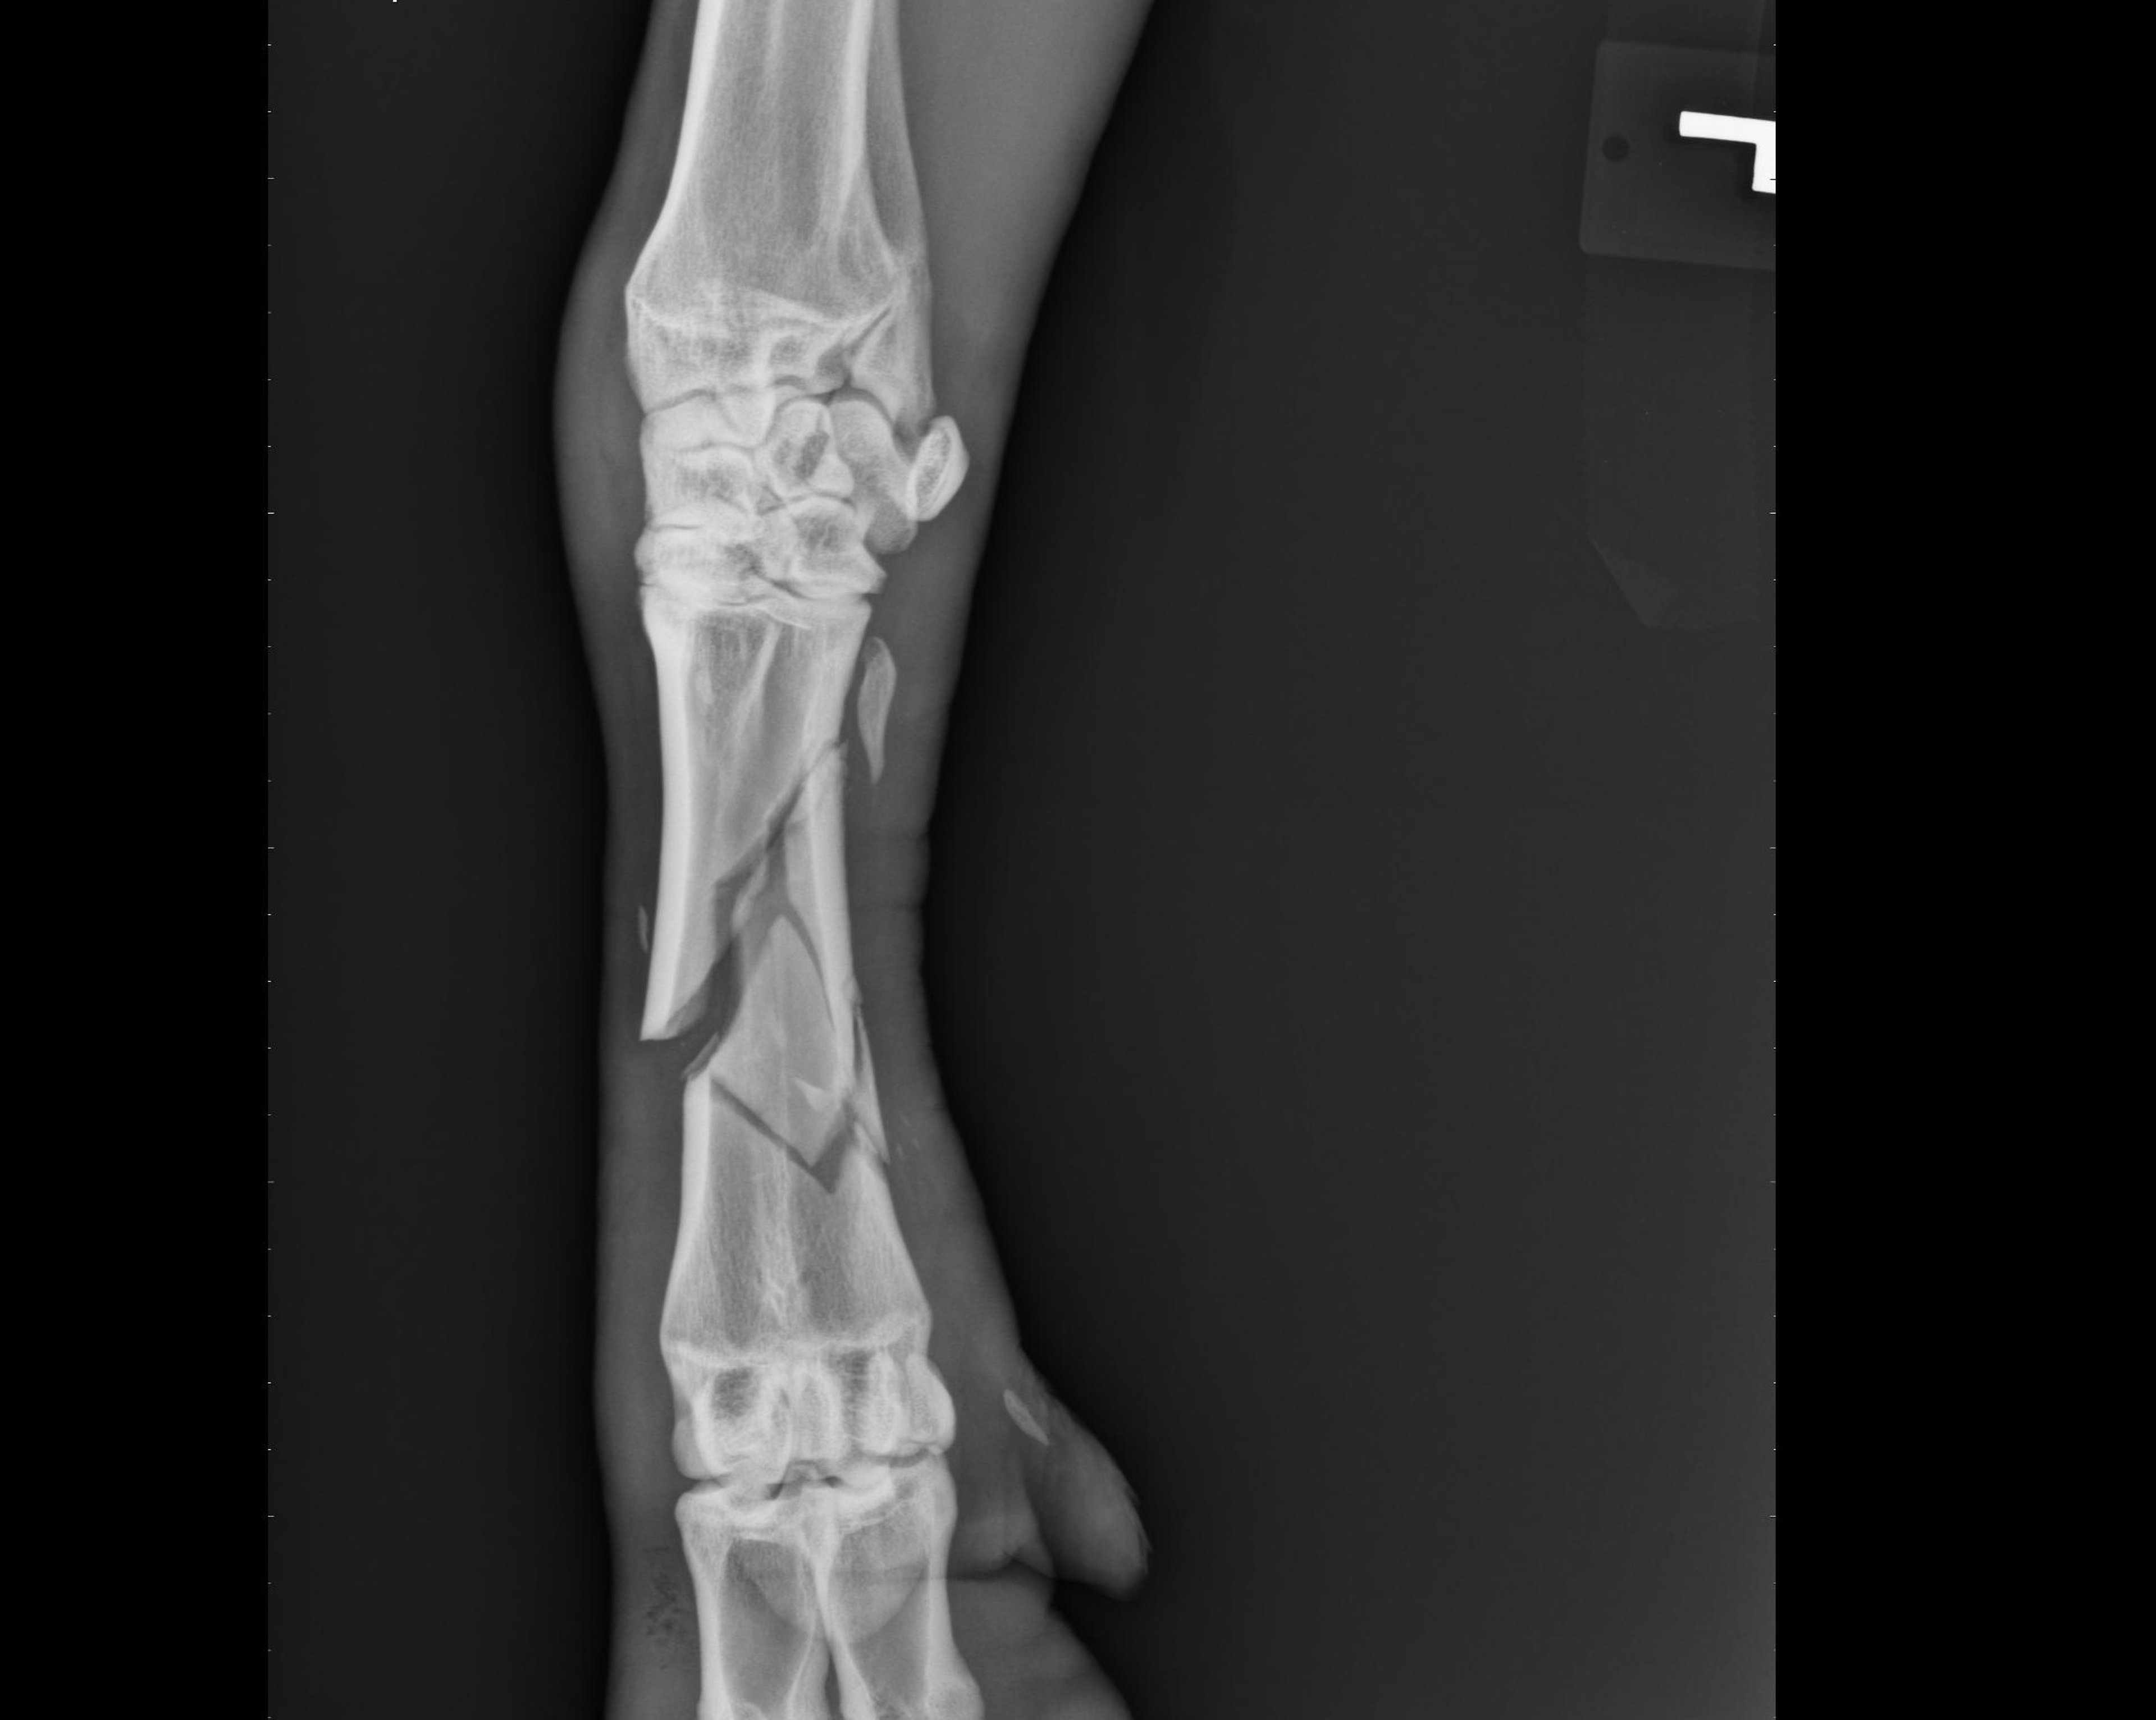

Goats, in general, are agile creatures; however, if frightened, they may attempt jumps that result in fractures or other injuries. Yards designed for goats that are infrequently handled should have a visual as well as physical barrier. Chain-link fences are often associated with limb fractures when used for goat enclosures. Shearing of Angora goats is a source of potential problems when the shearer’s comb cuts into or through the gastrocnemius tendon. If goats are attacked by dogs or wild canines and survive, they often have multiple traumatic injuries that can include fractures.

Fortunately, most fractures of the lower limbs heal rapidly with external fixation and a cast. Orthopedic procedures suitable for large dogs can typically be used for fracture fixation.